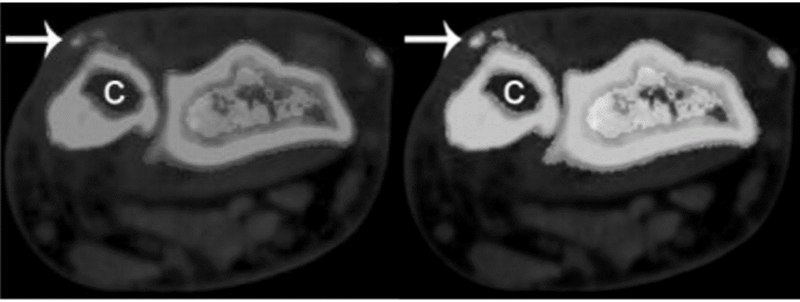

图2.双能计算机CT断层扫描显示远尺桡关节焦磷酸钙沉积